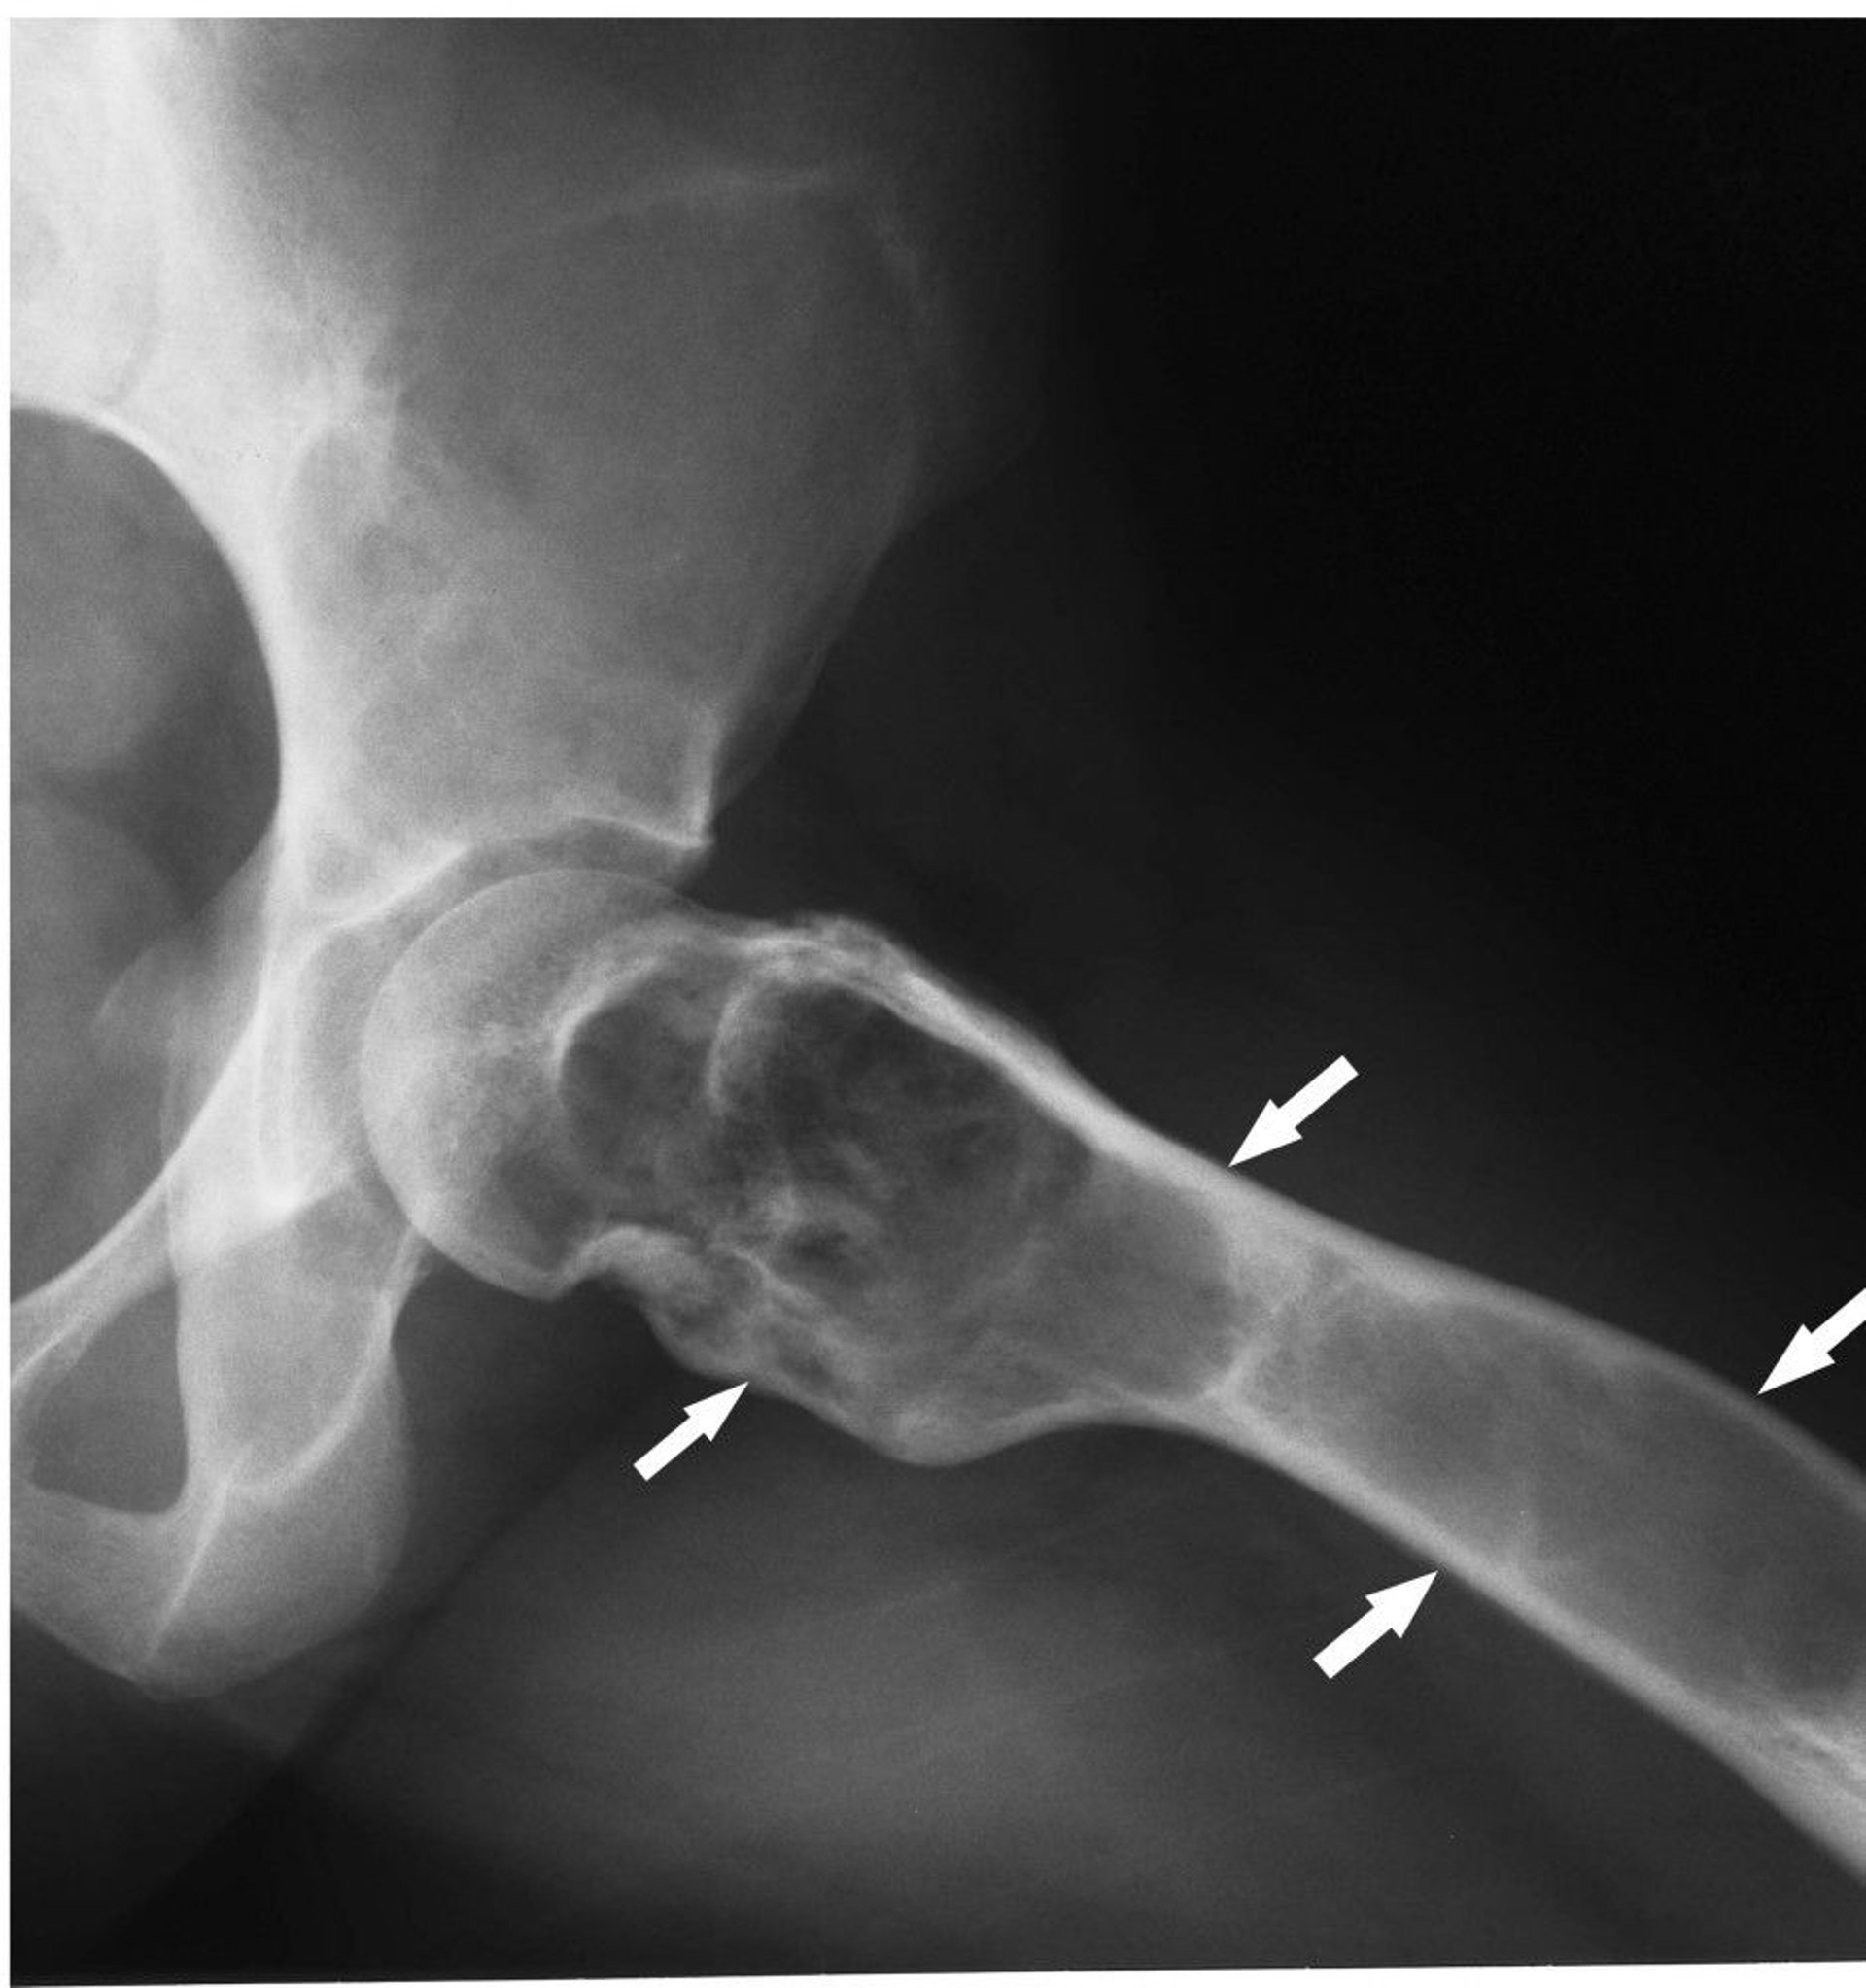

This radiograph of the hip shows fibrous dysplasia (arrows) with cortical expansion and ground-glass matrix.

Image courtesy of Michael J. Joyce, MD, and Hakan Ilaslan, MD.